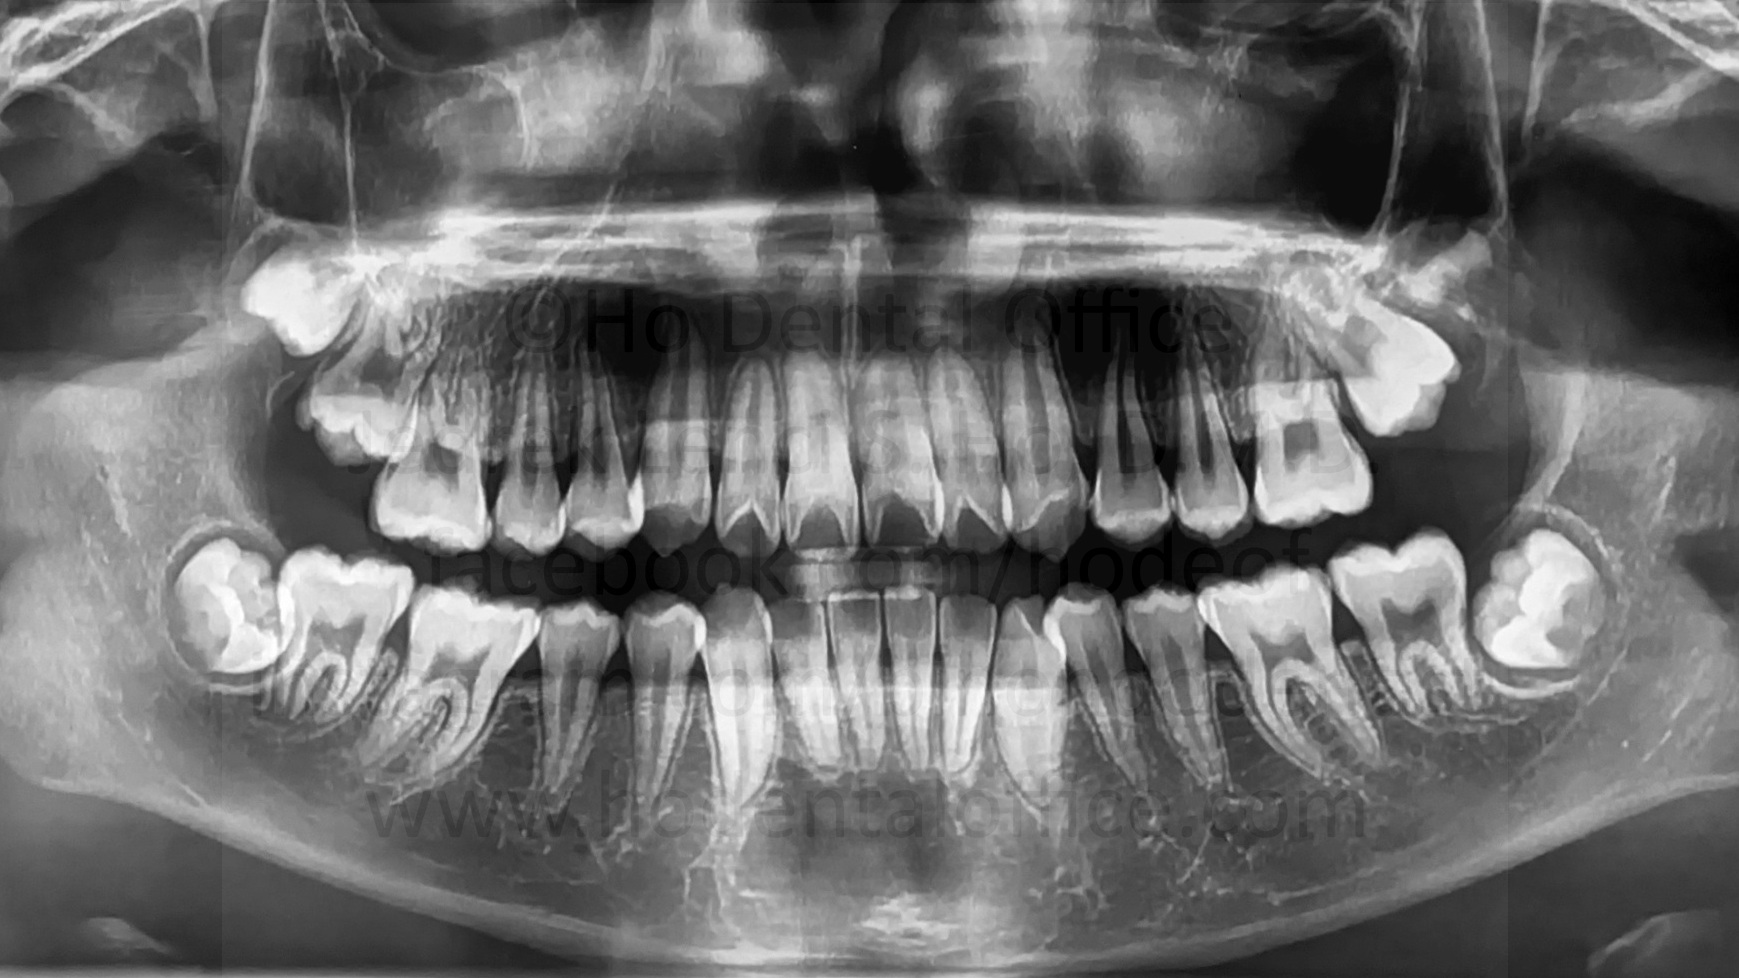

- prevention of bone loss - When impacted third molars (wisdom teeth) are taken out before they fully mature, chances are, the bone level behind the second molar will be higher. As the third molar fully matures, it also takes up more space thus resorbing more bone behind the second molar. Younger patients also have better healing than older patients, and so when the fully matured third molar is extracted from an older patient, there is a higher chance that the bone level behind the second molar is suboptimal, which may cause the second molar to be more wobbly because of poor bone support.

![]() | ![]() | ![]() |

| bone loss due to presence of third molars, note the bone level of the second molar on the side facing the third molar is already on the level of the second molar's roots | ||